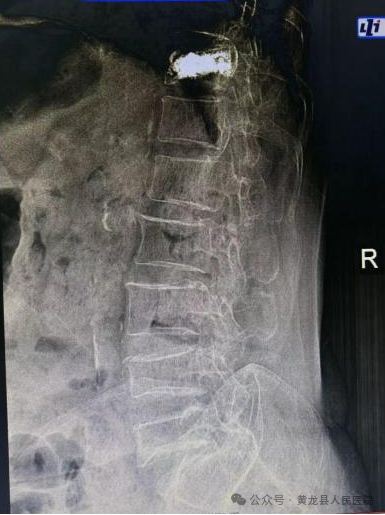

患者女,78岁,2023年3月不慎摔倒致胸腰背部疼痛,翻身、弯腰、下地活动严重受限。入院后X线检查示:腰1椎体压缩性骨折,结合患者具体情况,给予综合评估,给予微创经皮椎体成形手术,手术效果满意。2023年8月,患者再次不慎摔伤,致胸11椎体骨折,有了第一次微创手术经历,患者入院后果断选择微创经皮椎体成形手术治疗,手术顺利,达到预期效果,术后患者恢复较好,经过外科医护团队精心治疗和优质护理,患者顺利出院。患者及家属对整个就医感受很是满意,特送上锦旗向医务人员表示感谢。

术前MRI 和术后X线影像图片

患者女,88岁,因病理性骨质疏松导致胸腰背部疼痛,翻身、弯腰、下地活动严重受限。入院后行X线检查示:胸椎体压缩性骨折(胸11)。

术前术后X线影像